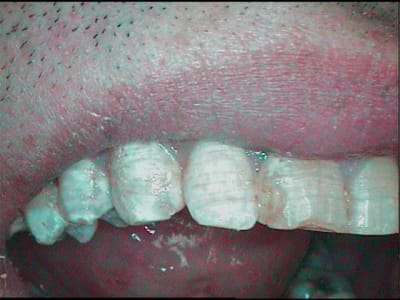

effectivement c'est un e amelogenese imparfaite a email pitted elle est rare c'est la fomme hypoplasique a email pitted le traitement apres conseil d'hygiene est le commpsite fluise qui comble le puit

en effet, une bonne hygiene, enseignée a l'époque des dents de lait (qui n'avaient pas d'amelogenese ) a limité le risque carieux....pour l'instant

pour abonder dans ton sens concernant l'heredité, ci joint une photo du papa, cependant moins avancé que sa fille

pour diverger cependant, l'hérédité n'inclue pas forcément, dans ce cas les atteintes obligatoires des lactéales, elles étaient indemnes a l'époque

quand j'ai vu le papa, j'ai pensé qu'une simple mise a plat des puits dans certaines régions auraient peut etre permis de limiter le risque carieux, je n'ai pas osé...